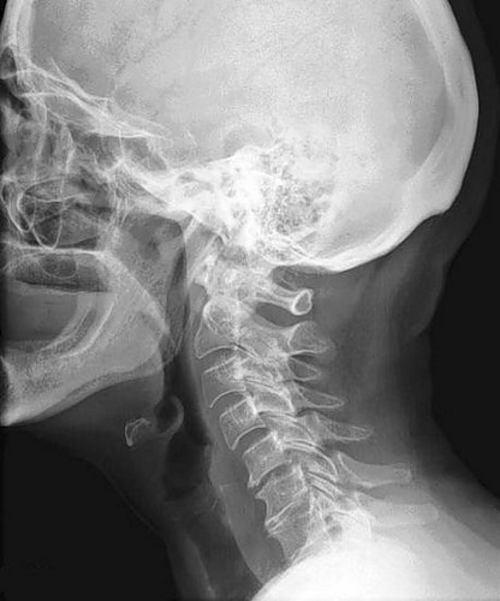

Спондилез чаще всего развивается в нижней части шейного отдела, где позвонки обладают наибольшей подвижностью. Местоположение пораженных позвонков можно увидеть на соответствующих изображениях.

- Рентгенография. На снимках можно увидеть состояние шейных позвонков и выявить изменения, такие как костные наросты.